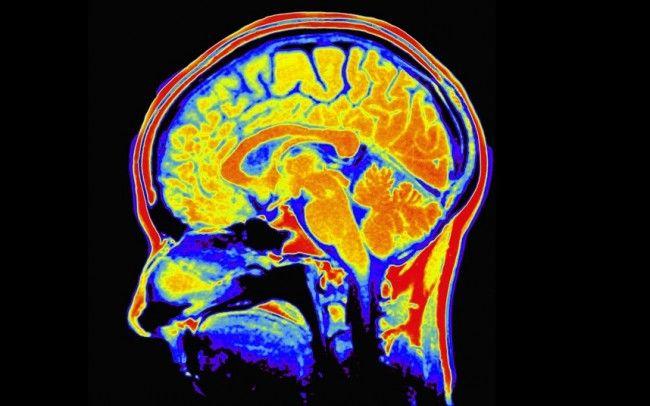

Creierul este în formă maximă în jurul vârstei de 22 de ani, şi se menţine aşa fără niciun efort suplimentar doar câţiva ani. Începând de la 27 de ani, îşi fac apariţia primele semne ale îmbătrânirii creierului, iar problemele se acutizează dacă nu stimulaţi suficient creierul.

Somnul permite creierului să consolideze noile cunoştinţe acumulate şi chiar să întregească amintirile care au fost uitate parţial, arată un studiu publicat în revista Nature. Concret, în timpul somnului, sunt consolidate legăturile dintre celulele nervoase ale creierului, lucru care stimulează procesul de învăţare şi memorare.

Pentru a ţine creierul în priză şi a preveni tulburările de memorie, organismul are nevoie şi de mişcare. „Creierul poate fi menţinut în formă şi prin exerciţiu fizic de intensitate moderată practicat zilnic”, subliniază medicul Hâncu. Exerciţiile fizice ajută la creşterea fluxului sanguin cerebral, lucru benefic pentru înmulţirea celulelor nervoase.